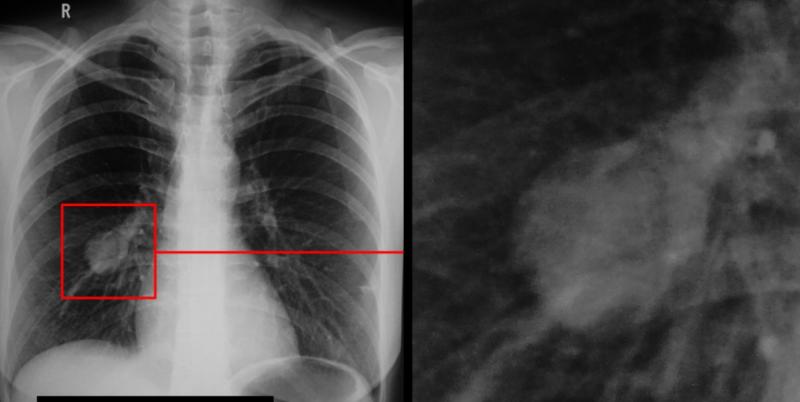

Красноярские медики запатентовали новый метод диагностики рака лёгких

Специалисты Центра ядерной медицины Федерального Сибирского научно-клинического центра ФМБА России разработали и запатентовали инновационный способ диагностики рака лёгких. Новый метод позволит выявлять заболевание на ранних стадиях и обнаруживать даже мельчайшие метастазы.

Как сообщили в ФМБА, технология основана на использовании молекул ДНК и РНК, способных связываться исключительно с опухолевыми клетками. Это обеспечивает высокую точность и минимизирует риск ложных результатов.

В настоящее время метод прошёл первый этап разработки и готовится к проведению клинических испытаний.